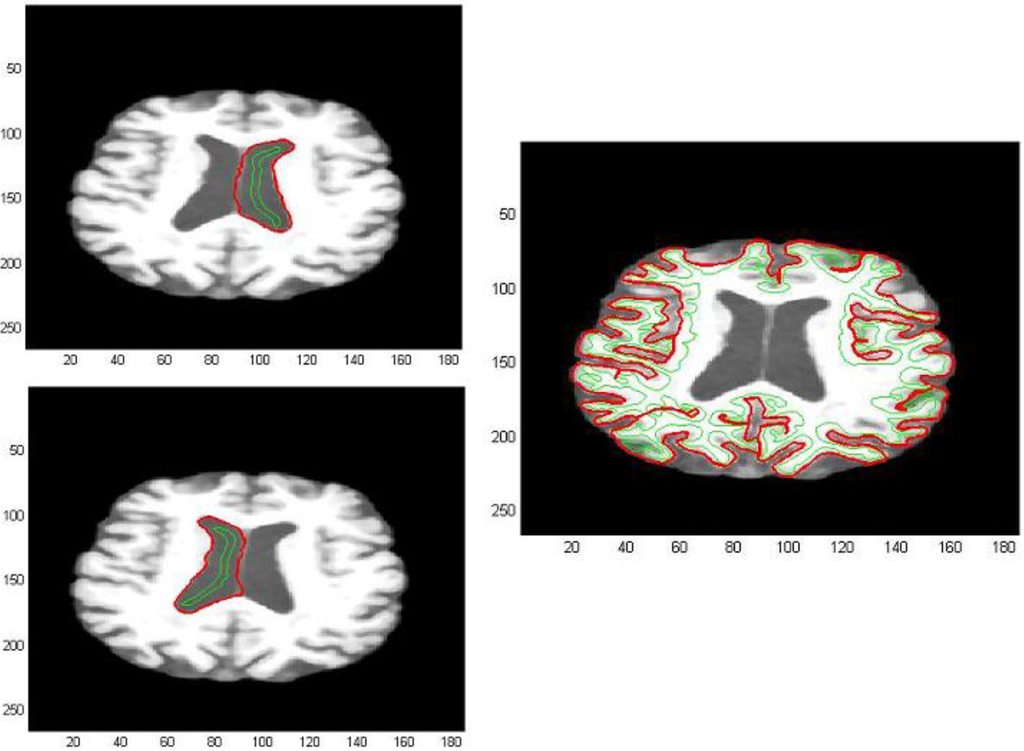

For what concerns DTI images, this approach is addressed to demarcate the areas with higher diffusivity of water molecules. We could note the high level of noise present in them; in order to perform a noise reduction, images are initially pre-processed applying a median digital filter (Figure 16). As previously mentioned, the most significant information of a grayscale FA map are taken from zones with high intensity levels corresponding to preferential directions of water diffusion, presumably along axonal bundles. Thus after analyzing the intensity distribution of image pixels (Figure 17 and Figure 18), we have obtained an image segmentation by using thresholds ranging from 180 to 210. Subsequently, edge extraction has been performed through an automatic selection of an initial contour from the level curves of the divergence map (Figure 18, Figure 19 and Figure 20).

Figure 16. (a) DTI image for a non-pathological subject; (b) Filtered FA map.

Figure 18. DTI image extraction for a non-pathological subject.

Figure 19. DTI image extraction for a non-pathological subject.

Figure 20. DTI image extraction for a pathological subject.